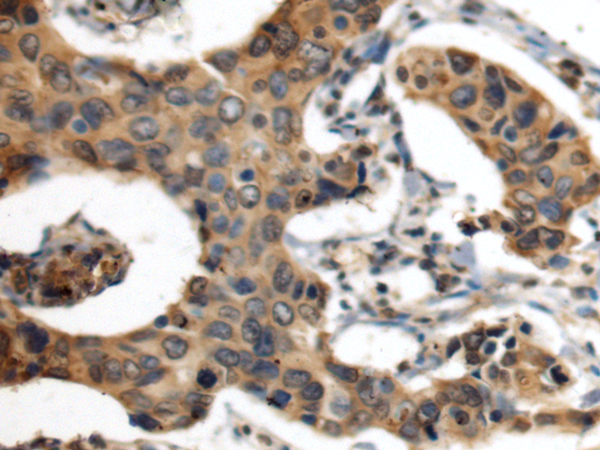

ELISA, IHC |

IHC positive control: |

Human breast cancer |

IHC Recommend dilution: |

100-300 |